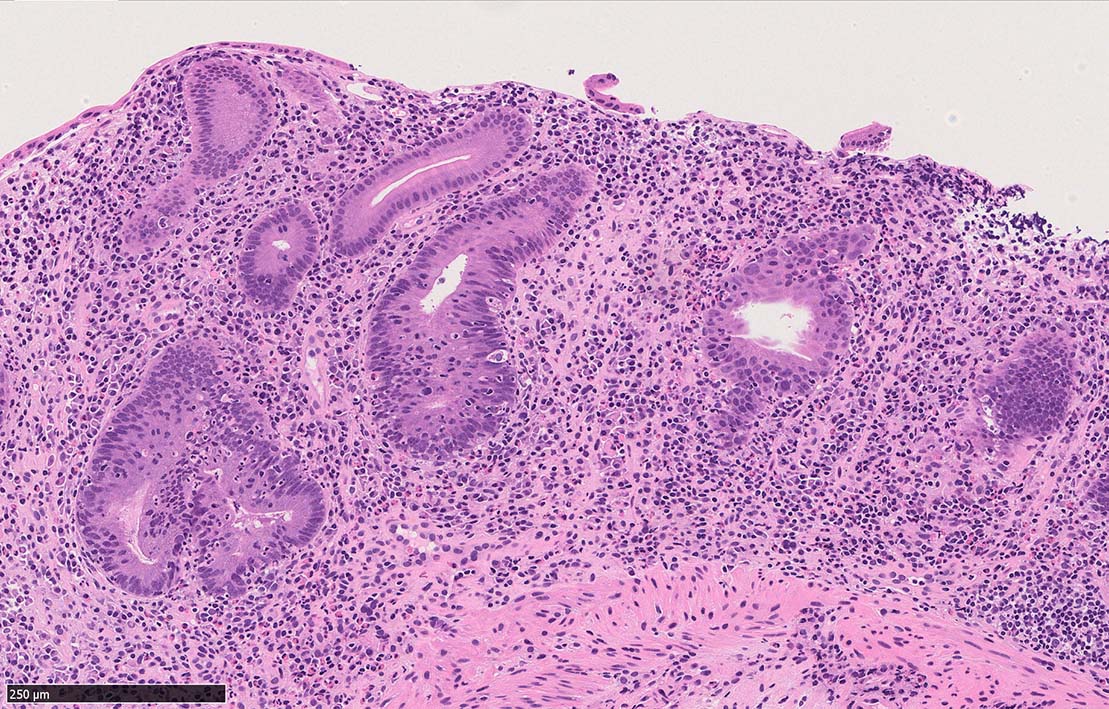

Case presentation

びらんを示す結腸粘膜. 陰窩はdeletion, 萎縮, distortionを呈する. 粘膜固有層には密な慢性炎症がみられ, 好酸球浸潤も多い.粘膜筋板へも炎症細胞浸潤が及ぶ.

UCのような, crypt abscess, cryptitisが認められる. 特徴的な所見として, apoptosis bodiesの増加が見られる.

陰窩に多数のapoptosis bodiesを認める.